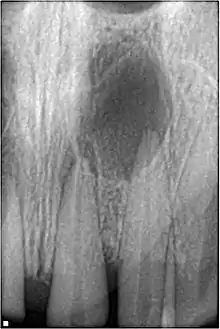

Sinusitis is inflammation of the paranasal air sinuses. Odontogenic sinusitis is an inflammatory condition of the paranasal sinuses that is the result of dental pathology, most often resulting from prior dentoalveolar procedures, infections of maxillary dentition, or maxillary dental trauma.[5] Infections associated with teeth may be responsible for approximately 20% of cases of maxillary sinusitis.[6] The cause of this situation is usually a periapical or periodontal infection of a maxillary posterior tooth, where the inflammatory exudate has eroded through the bone superiorly to drain into the maxillary sinus. Medical management and treatment of the underlying dental pathology remains a critical initial step in the treatment of odontogenic sinusitis, however recent literature suggests that a significant portion of patients may require endoscopic sinus surgery for successful disease resolution.[5] Once an odontogenic infection involves the maxillary sinus, it is possible that it may then spread to the orbit or to the ethmoid sinus.[6]